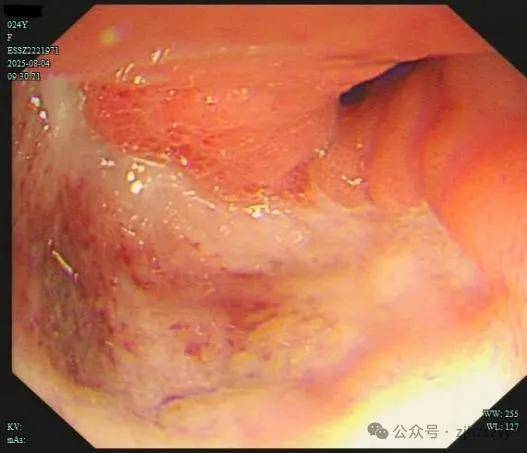

直到她开始频繁出现黑便,并在片场拍戏时几次呕血,才被同事紧急送往我院急诊。情况紧急,医生立即为小雯安排了急诊胃镜检查,发现她整个胃窦被一巨大的溃疡占据,黏膜组织变得僵硬、缺乏弹性,好似“皮革”一般。而随后的活检结果,更是给了这个年轻姑娘沉重一击——胃印戒细胞癌。

胃印戒细胞癌早期的隐匿性很强,在胃镜下表现也不明显,识别非常困难,可能表面看起来只是点、片状糜烂,而实际上已经多点生长。